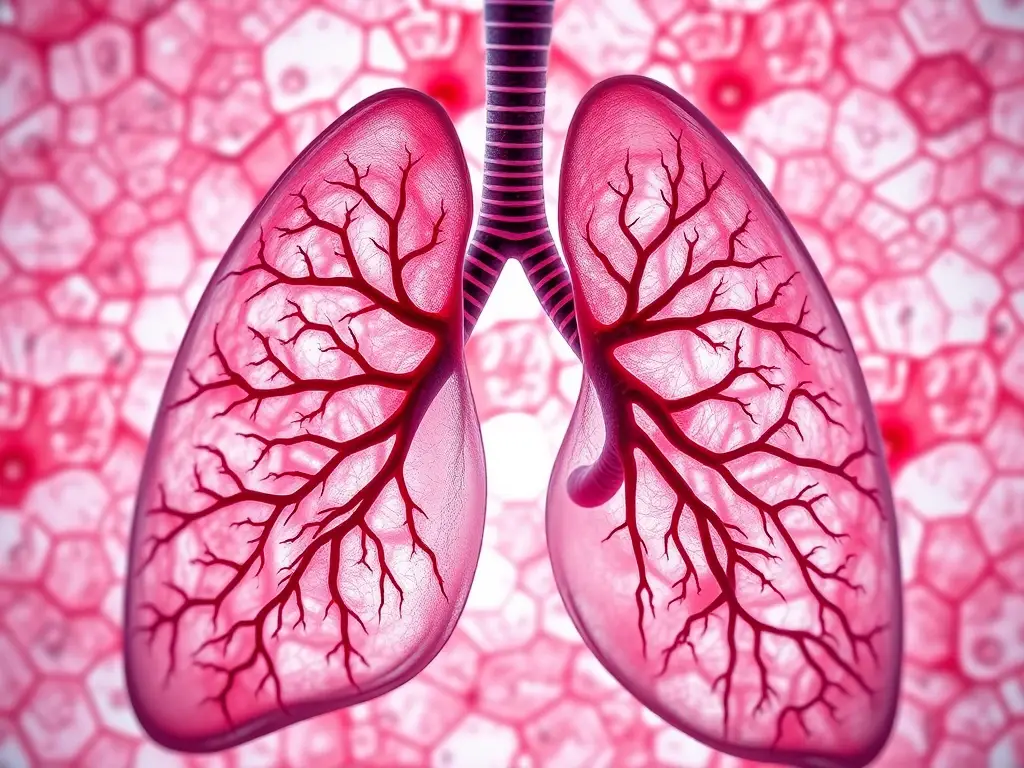

La respiración es un proceso fundamental para la vida en prácticamente todos los seres vivos, y aunque existen diversas formas de llevarla a cabo, la respiración pulmonar es quizás una de las más reconocibles y estudiadas. Este método, que implica la absorción de oxígeno del aire y la liberación de dióxido de carbono, se basa en la utilización de órganos especializados llamados pulmones. Estos órganos, con su intrincada estructura, permiten el crucial intercambio de gases necesario para mantener la energía y las funciones vitales de los organismos. La variedad de animales con respiración pulmonar es asombrosa, abarcando desde los mamíferos más grandes hasta pequeños invertebrados, demostrando la adaptabilidad de esta función a diferentes entornos y estilos de vida.

La importancia de la respiración pulmonar radica en su capacidad para proveer a las células con el oxígeno necesario para la respiración celular, el proceso que genera energía. Sin este intercambio constante de gases, la vida tal como la conocemos sería imposible. Los pulmones, con sus millones de pequeños sacos de aire llamados alvéolos, maximizan la superficie de contacto entre el aire y la sangre, facilitando así la transferencia eficiente de oxígeno a la sangre y de dióxido de carbono desde la sangre al aire. Este proceso, aunque invisible a simple vista, es la base de toda actividad biológica.

Los vertebrados terrestres, que incluyen mamíferos, aves, reptiles y anfibios, son los ejemplos más comunes de animales que respiran por los pulmones. En los mamíferos, como nosotros los humanos, los pulmones son estructuras esponjosas y altamente vascularizadas situadas dentro de la cavidad torácica. La inhalación se produce por la contracción del diafragma y los músculos intercostales, expandiendo el volumen de la cavidad torácica y creando una presión negativa que aspira el aire hacia los pulmones. La exhalación es un proceso pasivo que ocurre cuando los músculos se relajan y la cavidad torácica vuelve a su tamaño original.